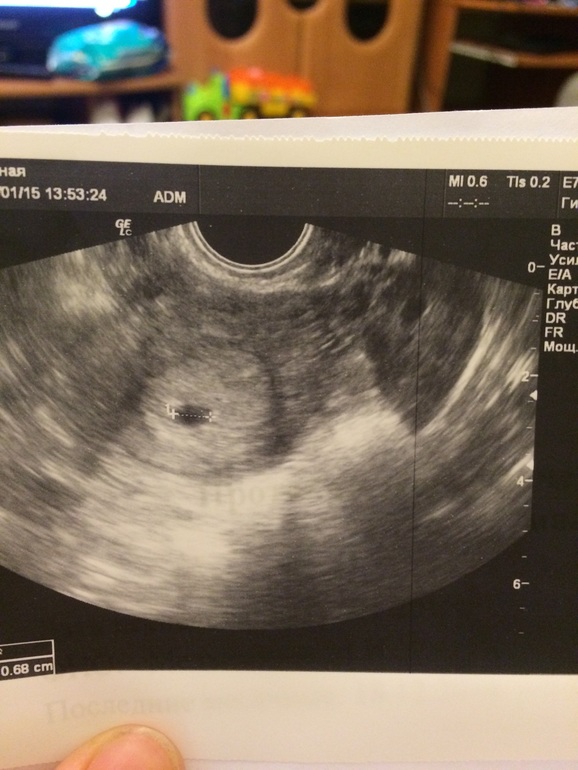

Вопросы про УЗИ, обследования и анализы: что, где, как, когда?Девочки, всем привет! Делала УЗИ, сказали сделать через две недели, срок маленький, бла-бла... Так вот, пришла домой, смотрю на снимок и не пойму, вижу один эмбрион (не знаю, как назвать) и рядом такой же... Это что? С первой беременностью только один эмбрион на снимки был на ранних сроках.

на вашем фото ничегошеньки не видно, но второй эмбрион-это скорее всего желточный мешочек! он должен находиться прям рядом с эмбрионом, а по факту он к эмбриону прикреплён. потом он исчезает))

так вы все таки что имели ввиду? отражение матки справа, или невидимый на фото второй эмбрион внутри плодного яйца?

А где вы второй то видите? Это справа чтоли? Так там отражение матки с эмбрионом.